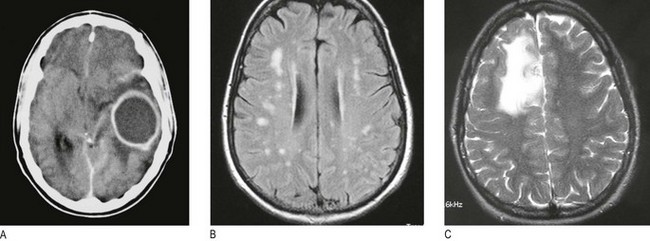

Fig. 11.33 Scanning of the head:

(A) DaTSCAN scan showing the distribution of blood flow on cross-section of the brain. (B) MR scan showing ischaemic stroke T2 imaging demonstrates bilateral occipital infarction and bilateral hemisphere lacunar infarction. (C) Unenhanced CT scan showing subarachnoid blood in both sylvian fissures (white arrows) and early hydrocephalus, with temporal horns of the lateral ventricles visible (black arrows).